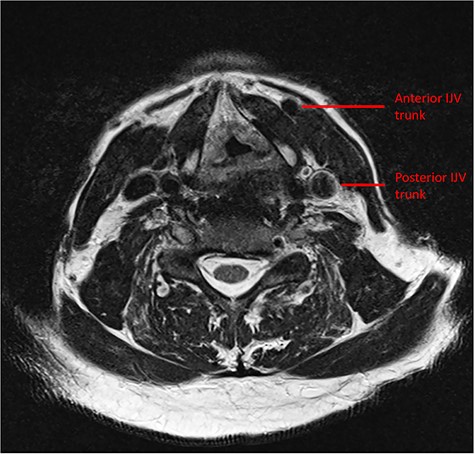

Preoperative MRI demonstrating the duplicate trunks of the left IJV.

Intraoperatively, during the ND, a rudimentary only external jugular vein (EJV) was identified. Whilst developing the platysma flap, a large venous vessel was identified antero-medially to the SCM and preserved (Fig. 1). This was subsequently found to represent the anterior trunk of the duplicated IJV. Then, when developing the levels II–III–IV of the ND specimen the posterior segment of the IJV was identified and preserved. The course of IJV duplication began at level II under the posterior belly of the DGM. The bifurcation continued to level IV, beneath the omohyoid muscle. Both segments were ~9 cm in length and all the main IJV tributaries (lingual, facial and middle thyroid veins) were draining into the anterior segment (Fig. 2). The space between the two segments was occupied by the common carotid artery, its bulb and its bifurcation. The SAN was found to be running under the two IJV trunks (Fig. 3).